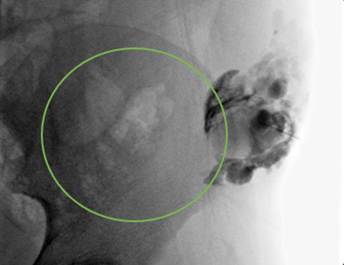

Infante de ocho años, llevado al servicio de urgencias por masa abdominal dolorosa de un año de evolución, localizada en el flanco izquierdo. Al examen físico se encontró una masa violácea, firme y dolorosa en el flanco izquierdo, sobre la cresta ilíaca, de aproximadamente 8x4 cm. La ecografía abdominal informó una lesión quística multiseptada versus estructuras cilíndricas vasculares dilatadas de 13x3,2x2,1 cm, sin flujo Doppler en su interior, sin componente sólido (Figura 2). En la resonancia nuclear magnética (RNM) se encontró una masa que deformaba la pared del flanco izquierdo y la pelvis izquierda, con septos intermedios, probablemente relacionado con hematomas (Figura 3). Se consideró malformación de bajo flujo, posiblemente linfática, y se le realizó manejo percutáneo con agentes esclerosantes (bleomicina 15 UI) (Figura 4), siendo dado de alta, con reingreso al mes por dolor abdominal y vómito. Una nueva ecografía abdominal informó hallazgos similares a los iniciales, además de cambios inflamatorios adyacentes. Se realizó manejo únicamente con antiinflamatorio no esteroideo con resolución de los síntomas. Posteriormente no se logró realizar seguimiento del paciente.